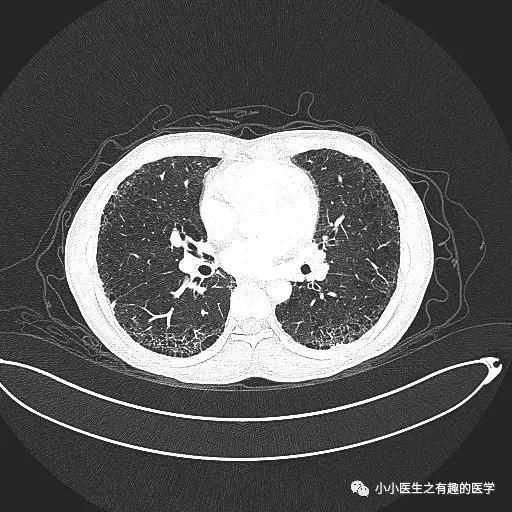

乌漆嘛黑的是肺气肿。

间质性肺炎 合并 肺气肿